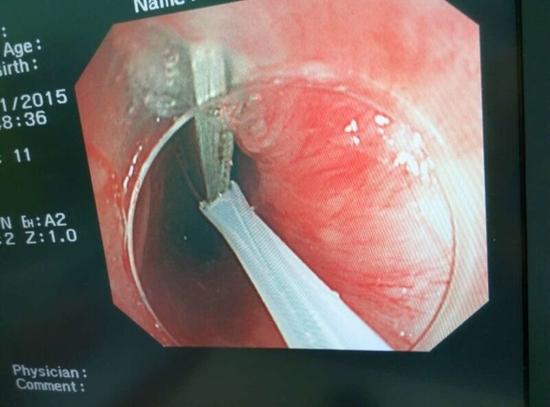

醫(yī)生從華先生胃里取出的鑷子和打火機(jī)

隨后,范醫(yī)生先用圈套器套取出了長10厘米的鑷子,再一個一個地取出了打火機(jī)。整個取出過程小心謹(jǐn)慎而又一氣呵成,只用了不到10分鐘。